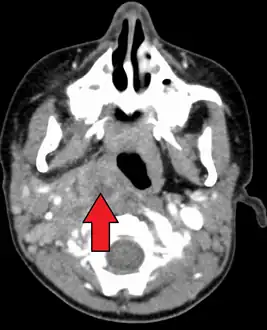

A computed tomography (CT) scan is the definitive diagnostic imaging test.[4]

X-ray of the neck often (80% of the time) shows swelling of the retropharyngeal space in affected individuals. If the retropharyngeal space is more than half of the size of the C2 vertebra, it may indicate retropharyngeal abscess.[5]